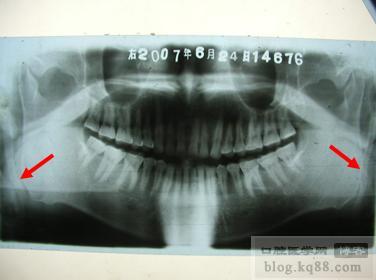

圖10常規(guī)曲面體層片

圖10

1 通常診斷莖突過長綜合征的主要影像學(xué)檢查為X線平片(莖突正側(cè)位片和曲面體層片),莖突因其位置特殊,傳統(tǒng)X線平片投照時可引起影像放大和扭曲,以及莖突和周圍骨質(zhì)重疊,不能清晰顯示莖突的全貌,使得莖突長度測量的準(zhǔn)確性受到限制,影響該病的正確診斷。